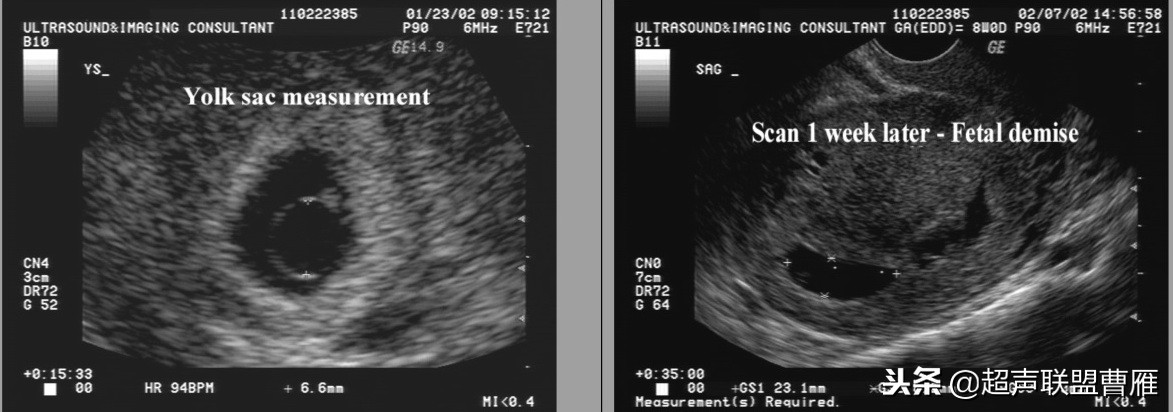

钙化卵黄囊6.6mm,一周后胚胎死亡

· 卵黄囊不规则或钙化:出现囊壁钙化或者增厚等形态改变以及囊壁缺损,提示 卵黄囊功能衰退与营养障碍,预示妊娠结局不良。一般情况下,出现钙化通常胚胎已停育。

卵黄囊的大小与形态异常与胚胎的发育是否正常关系密切。卵黄囊增大,直径超过6.1cm,胚胎的预后不良。

卵黄囊的大小与形态异常与胚胎的发育是否正常关系密切。,形态异常的卵黄囊预后不良。